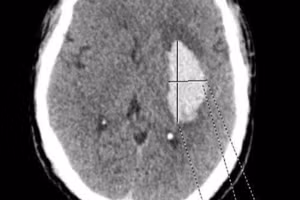

Dinh dưỡng rất quan trọng trong quá trình phục hồi chấn thương não vì cả não và cơ thể đều cần chất dinh dưỡng phù hợp. Thực phẩm cung cấp năng lượng và chất dinh dưỡng cho sự hồi phục não sau mổ. Một chế độ ăn hợp lý giúp cải thiện cả sức khỏe tổng thể và phục hồi não.